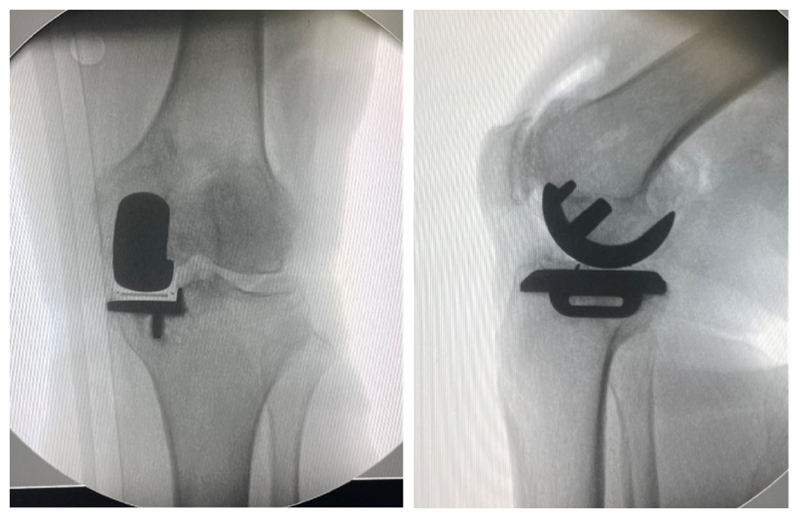

非骨对骨内侧OA单髁置换术(PTCL

术前

术后检查

一般认为应力位片非骨对骨接触,可以借助MRI或术中关节镜探查明确原因,对于残留软骨<25%可考虑单髁置换。总体而言,非骨对骨单髁置换手术疗效低于骨对骨单髁置换术。

活动度小于90度内侧单髁置换术(ROM < 90°)

经典的单髁手术一般膝关节需要至少屈曲至110°,术前低于90°一般不适合单髁置换。需要明确术前屈曲受限的具体原因,对于屈曲受限因后方骨赘增生阻挡的病例术中可以改善屈曲度。部分病例可能术后仍然不能恢复正常的屈曲度,功能一般不受影响。